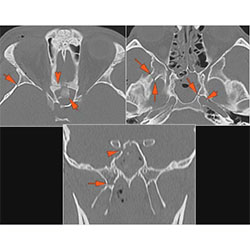

Right Temporal Bone

The external auditory canal shows abnormal soft tissue thickening.

The roof of the mastoid and/or middle ear is fractured.

A possible meningocele and/or encephalocele or CSF leak is present.

The ossicles, in particular the incus long process, the incudostapedial joint and stapes are fractured or dislocated.

The facial canal including the labyrinthine, tympanic and descending portions and nerve are fractured.

The inner ear including the lateral semicircular canals, vestibule and/or cochlea is fractured or otherwise abnormal.

There is subperiosteal, epidural or subdural hematoma along the roof of the mastoid or middle ear or the superior and posterior (intracranial) surfaces of the petrous portion of the temporal bone.

Left Temporal Bone